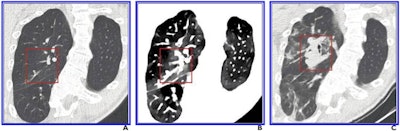

In particular, AI is helping clinicians better identify pulmonary embolism (PE) on CT angiography (CTA) -- and not only from PE studies but also on routine exams, according to Dr. Seth Kligerman, chief of cardiothoracic imaging at University of California, San Diego Health.

In fact, in October, AI software developer Aidoc secured clearance from the U.S. Food and Drug Administration (FDA) for its computer-assisted triage technology for marking incidental pulmonary embolism on CT scans and notifying radiologists about the findings.

AI for CT is also being used for lung density mapping and lung nodule detection, although in the latter area it may still be too sensitive, according to Kligerman.

"There are numerous AI-based tools and applications being developed for cardiothoracic CT, and if these applications are going to be successful, they need to be customizable in regard to each user's preference," he said. "Some users want an algorithm that will be nearly 100% sensitive and are willing to sift through numerous false-positive findings to achieve that goal. Others are willing to give up some degree of sensitivity to reduce the number of false-positive findings. It's hard to find a true 'sweet spot' that will fit for everyone, so these things should be adjustable."